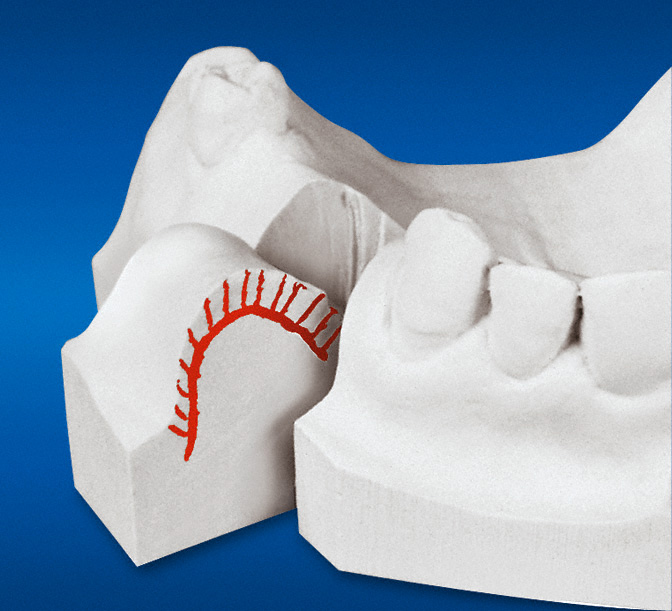

Für ein Implantat werden sowohl eine Mindest-Knochentiefe als auch ein Sicherheitsabstand im Unterkiefer zum Nervenkanal vorausgesetzt. Die Knochentiefe wird durch spezielle Röntgendiagnostik ermittelt.

Durch die Computertomographie kann die Lage der später zu setzenden Implantate im Vorfeld schon auf den Millimeter bestimmt werden.